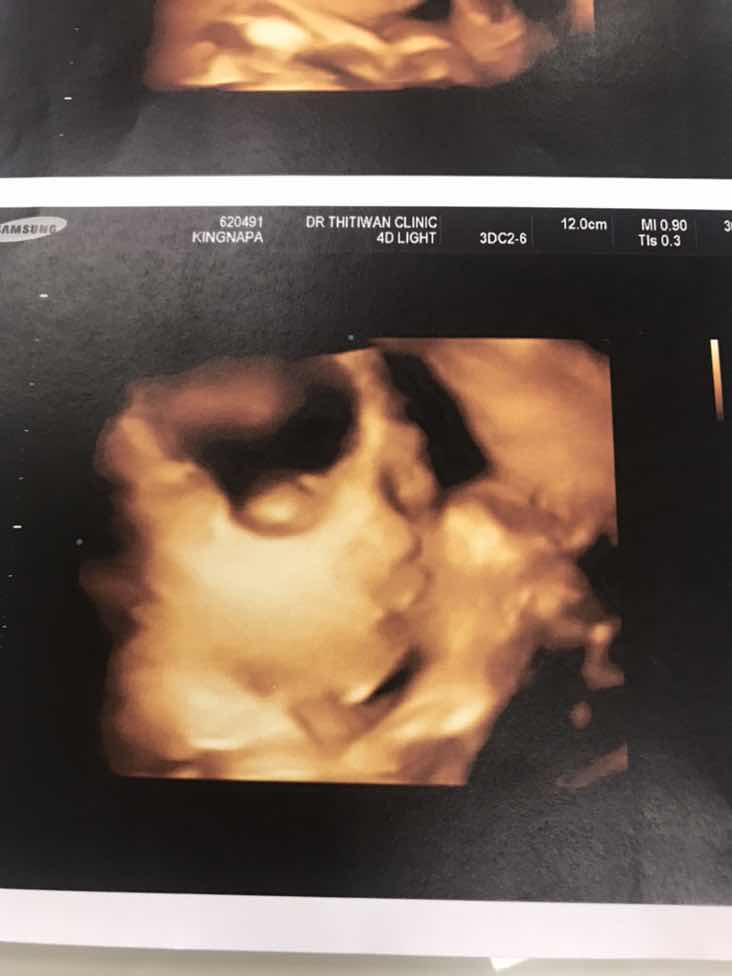

อัลตราซาวด์ 4 มิติ

มีแม่ๆคนไหน ซาวด์ 4 มิติบ้างไหมค่ะ ราคาประมาณเท่าไหร่กัน ถ้าน้องอยู่ท่าตามภาพที่โพส จะเห็นหน้าน้องไหมค่ะ 32 วีคค่ะ อยากเห็นหน้าลูก แต่หันตูดให้อย่างเดียวเลยค่ะ ?